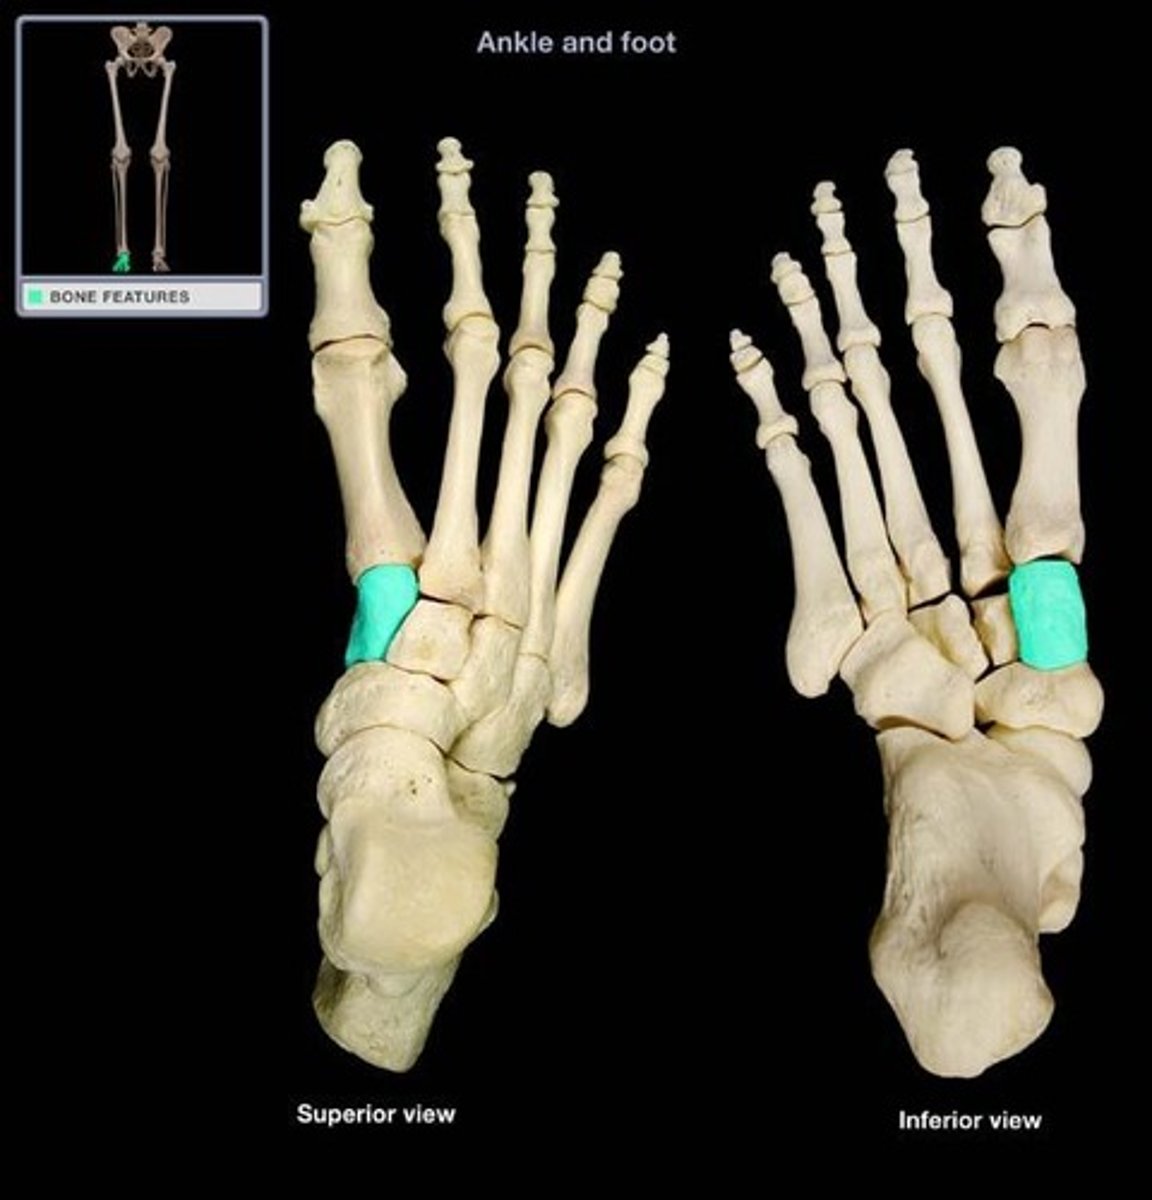

Medial Cuneiform

What is the term of the bones highlighted in green?

Intermediate Cuneiform

Lateral Cuneiform

Cuboid

Metatarsals

Phalanges of the Foot